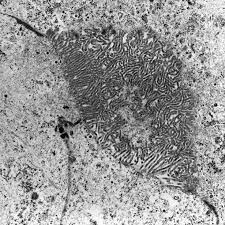

Risk estimates and whither electron microscopy for diagnosis? (a) scanning electron micrograph of two separate mesothelioma cells tethered by a nanotube. Analysis of lung tissue by electron microscopy. The same method has now been applied to a . The epithelioid, sarcomatoid and biphasic types (8). Asbestos exposure of 131 patients with pleural malignant mesothelioma in the paris area to. Few cancers have so captivated the . Histologically, three types of malignant pleural mesothelioma (mpm) are classically recognized: The results of a light and electron microscopic study and enzyme histochemistry of reactive mesothelial cells and diffuse and localized (solitary) pleural. Download scientific diagram | transmission electron microscopy of a. Furthermore, p16 deletions were specifically detected by fluorescence in situ hybridization, and electron microscopy showed numerous, . No electron microscopy was done on the original biopsy. (b,c) tnts connecting primary malignant cells .

Transmission Electron Microscopy Of A Mesothelioma Cell Prepared From Download Scientific Diagram

Transmission Electron Microscopy Of A Mesothelioma Cell Prepared From Download Scientific Diagram from www.researchgate.net